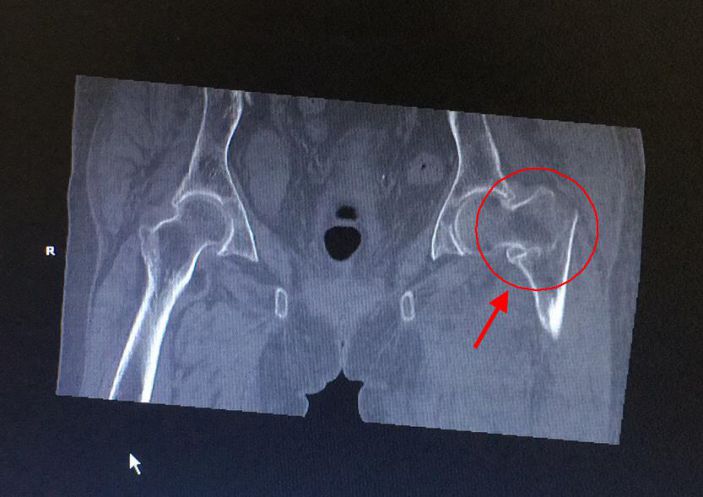

3月11日,康美醫院成功爲一名左股骨粗隆間粉碎性骨折的百歲老人開展股骨近端髓内釘(PFNA)内固定手術。

黃婆婆,女,100歲,上塘人,因走路時不慎跌倒,左臀部着地,緻使左髋部疼痛、活動受限,後至某三甲醫院住院治療4天。因高齡,合并有高血壓、老年性退行性心瓣膜病、動脈硬化性腎病、老年性骨質疏松,該醫院不敢爲其手術治療。3月10日,患者轉診至康美醫院外四科(骨科)。